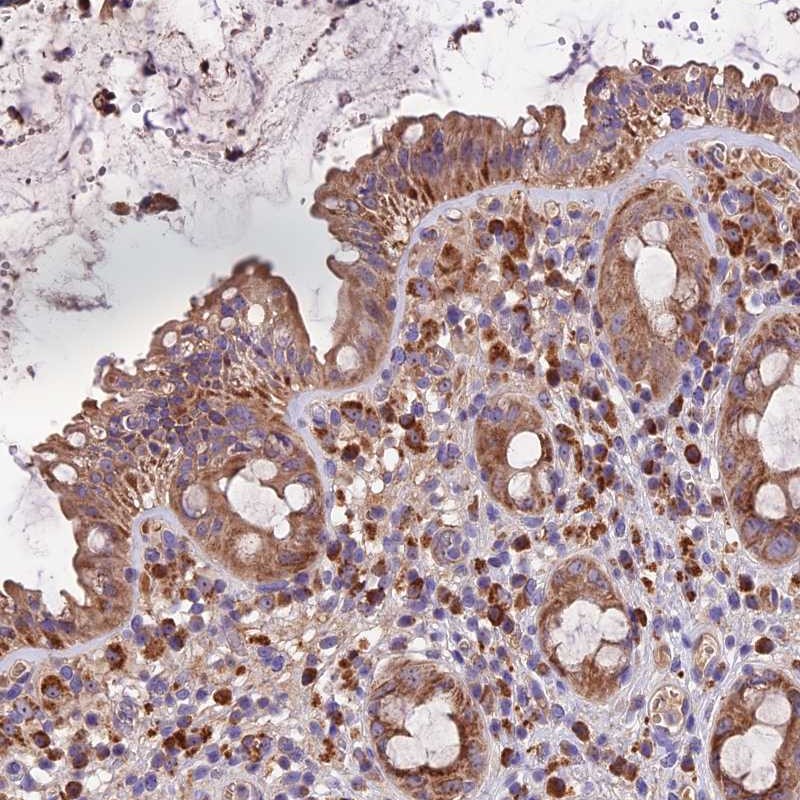

Immunohistochemical staining of human rectum shows moderate cytoplasmic positivity in glandular cells.